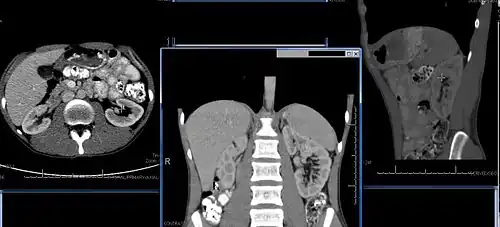

Chronic kidney disease (CKD) has been recognized as a leading public health problem worldwide. The global estimated prevalence of CKD is 13.4%, and patients with kidney failure needing renal replacement therapy are estimated between 5 and 7 million.[6] Procedures used in the management of kidney disease include chemical and microscopic examination of the urine (urinalysis), measurement of kidney function by calculating the estimated glomerular filtration rate (eGFR) using the serum creatinine; and kidney biopsy and CT scan to evaluate for abnormal anatomy. Dialysis and kidney transplantation are used to treat kidney failure; one (or both sequentially) of these are almost always used when renal function drops below 15%. Nephrectomy is frequently used to cure renal cell carcinoma.

Imaging

Renal ultrasonography is essential in the diagnosis and management of kidney-related diseases.[49] Other modalities, such as CT and MRI, should always be considered as supplementary imaging modalities in the assessment of renal disease.[49]